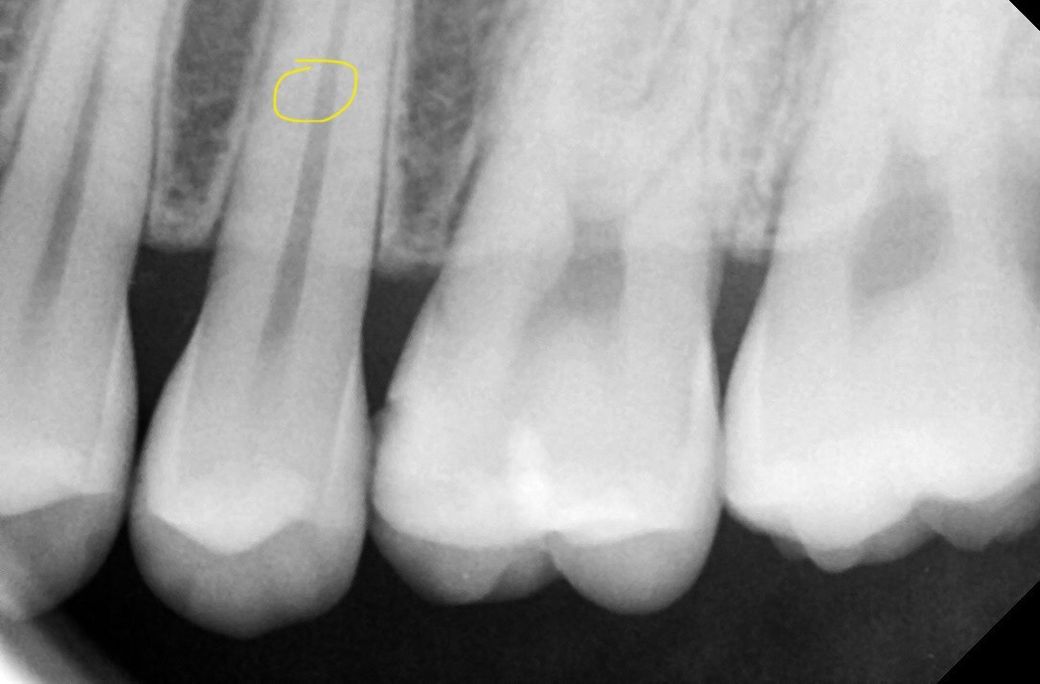

인접면 충치 꼭 치료 해야 하나요? 치과 2곳의 진료가 다릅니다 ㅠㅠ

기존에 다니는 치과에서 육안으로 인접면 충치를 발견하고 따로 엑스레이는 찍지 않고 인레이 35만원

진단 받았습니다

다른 치과는 엑스레이 찍어 보니 크기가 작아서

일단 좀 지켜보자 걱정이 된다면 2-3개월 뒤

다시 봐주겠다고 하셨습니다

부위는 왼쪽 위 3번째 입니다

사진 수정해서 좌우반전하거나 그러셨나요? 엑스레이는 왼쪽 위 작은 어금니이고, 임상사진은 오른쪽 위로 추정됩니다.

충치가 육안으로 보이지만 사진상으로 보이지 않는 경우에는 충치가 많이 진행되지 않았을 가능성이 있습니다. 인접면 충치의 경우에는 일반적으로 인레이라고 하는 보철물 치료를 하게 됩니다.